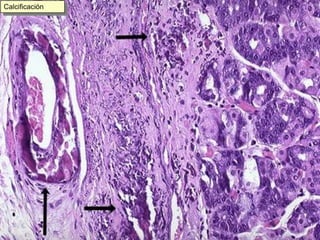

Este documento resume diferentes tipos de necrosis y otros procesos patológicos encontrados en anatomía patológica general. Describe necrosis coagulativa como infartos de miocardio y riñón, necrosis licuefactiva como infartos cerebrales, y otros tipos como necrosis grasa pancreática y necrosis caseosa en tuberculosis pulmonar. También cubre procesos como apoptosis, atrofia, hipertrofia, hiperplasia, metaplasia, displasia, y acumulaciones de sustancias como hemosiderina, amiloide y calcificaciones.